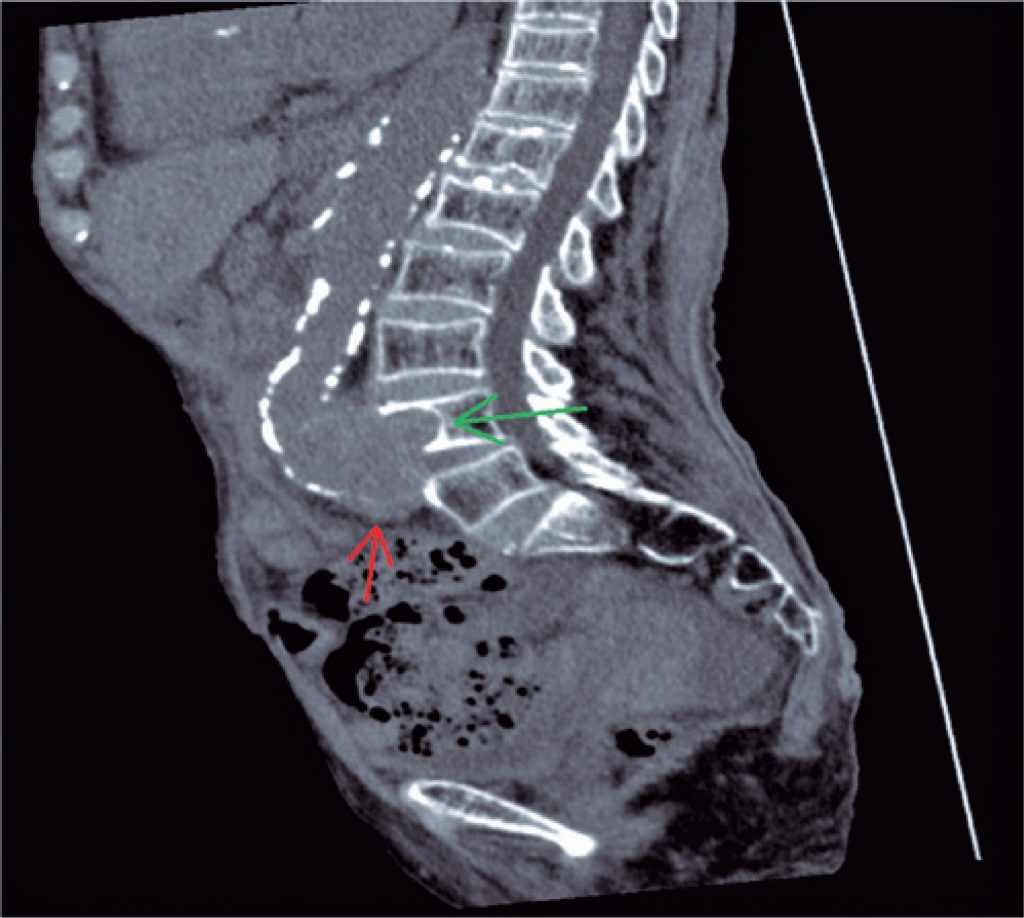

The computed tomography sections ( and ) showed a fusiform aneurysm in the aortoiliac bifurcation, extending up to the right iliac artery. This aneurysm was causing erosion of the anterior aspect of L4 vertebral body, with bone remodeling, marked by subjacent cortical sclerosis.